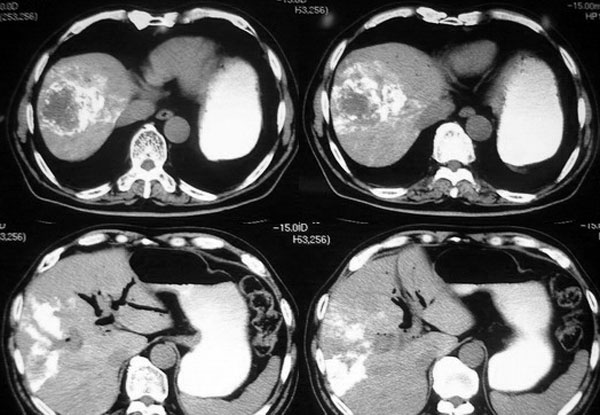

以下是引用逸风在2006-8-26 17:37:00的发言:[br]ct显示:\"壶腹癌肝转移\"行介入碘油栓塞术及胆总管内支架植入术后,肝右叶斑片状高密度碘油弥散,肝左叶见多个结节样低密度病灶,边缘清晰,肝左叶肝内胆管内气体影聚集.胆总管通常,腹膜后未见明显淋巴结肿大,片内所见其他未见明显异常.[br]诊断:1.壶腹癌肝转移\"行介入碘油栓塞术及胆总管内支架植入术后改变;2.肝左叶转移瘤,请与原片对比观察.